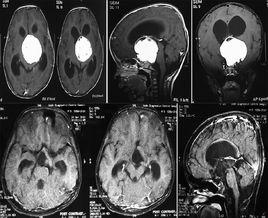

(一)CT、MRI檢查:

垂體癌及其他惡性腫瘤的CT與MRI影像表現不具特徵性。病程短,發展快。瘤體一般較大,形態多不規則,瘤體內密度不均,常有液化壞死區所呈現的低密度或長T1信號,長T2信號等影像表現。向鞍上及鞍旁發展,易造成周圍結構的明顯侵犯和破壞,尤其海綿竇有侵犯或有鄰近神經組織侵犯者應高度懷疑其為惡性。一般難以與侵襲性垂體腺瘤相鑑別。